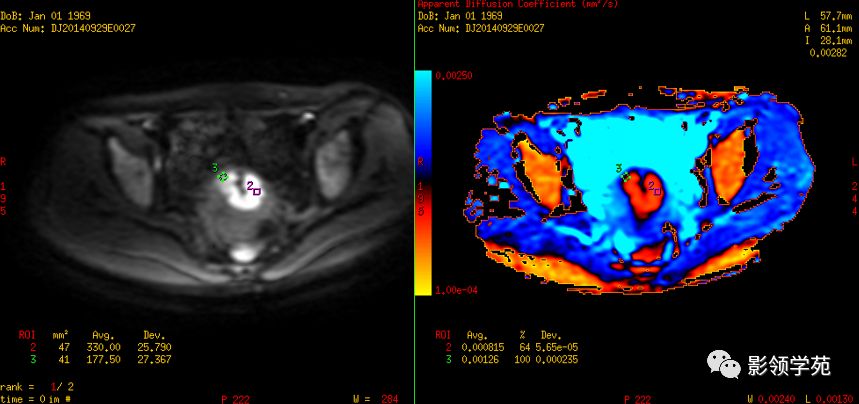

DWI:局限性高信号,癌组织ADC值<癌旁组织<小于正常宫颈组织

IIA期